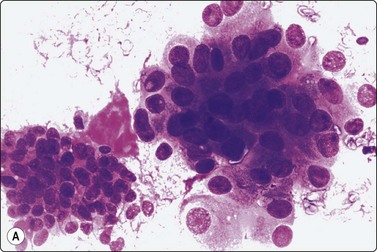

Squamous cell carcinoma (Figs 4.2 and 4.6)

Squamous cell carcinoma (SCC) is by far the commonest type of carcinoma encountered in the head and neck. Diagnostic criteria are listed in Chapter 8. Lymph node metastases of well-differentiated squamous carcinoma, particularly those arising in the Waldeyer’s ring, have a tendency to undergo liquefactive degeneration (see Fig. 4.3).41 The existence of primary SCC arising in a pre-existing branchial cyst has been doubted and is, in any case, an extremely rare event.42 The distinction from non-neoplastic cysts, mainly branchial cysts has been discussed above. Non-keratinizing squamous cell carcinoma may be represented in smears mainly by small basaloid cells in which case the differential diagnosis includes basal cell carcinoma, pilomatrixoma, poorly differentiated adenoid cystic carcinoma and other small cell tumors. Cells from a poorly differentiated squamous cell carcinoma have large vesicular nuclei and macronucleoli and resemble other anaplastic tumors such as melanoma and large cell lymphoma (Fig. 4.6).

image

Fig. 4.6 Squamous cell carcinoma

Mainly poorly differentiated malignant cells with large vesicular nuclei and large nucleoli; a few squamous and keratinized cells. FNB smears of cervical lymph node metastasis from squamous carcinoma of larynx (A, MGG; B, Pap, HP).